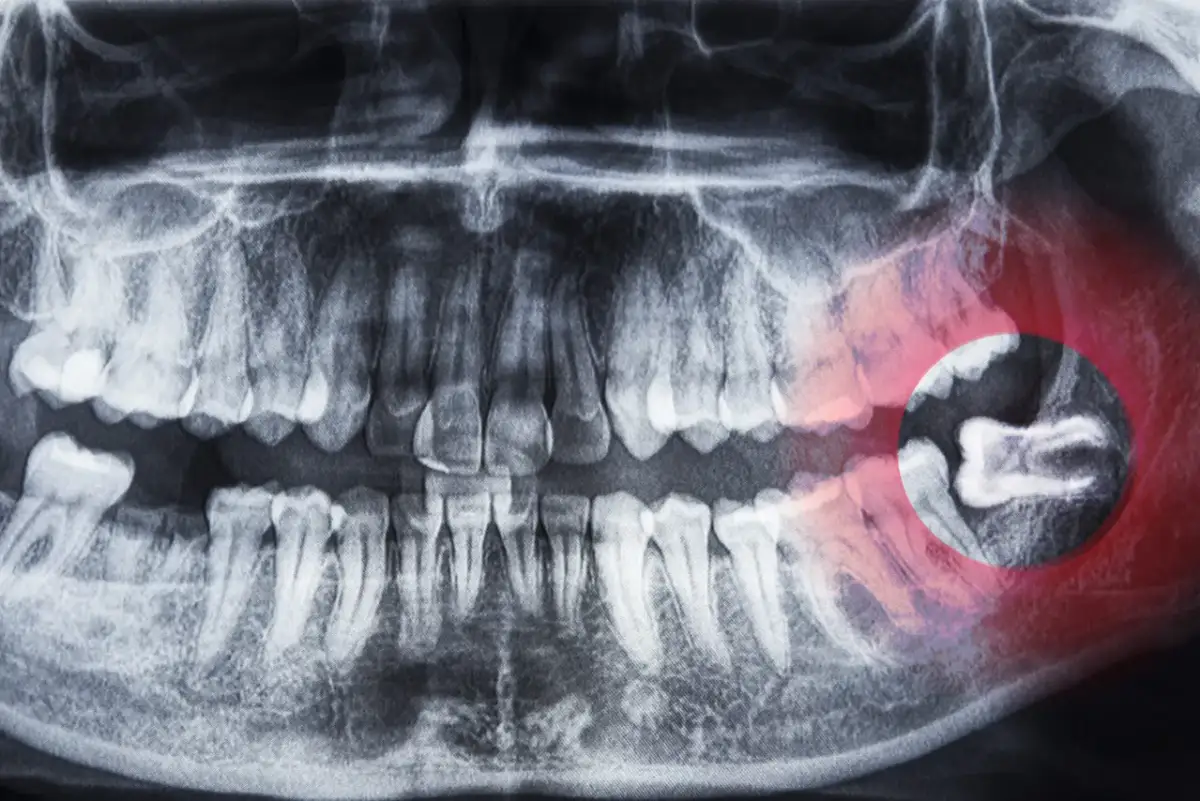

Nie zawsze trzeba decydować się na ekstrakcję zęba. Jednak w niektórych sytuacjach jest to jedyne rozwiązanie. Zaawansowana próchnica, stany zapalne czy urazy mechaniczne mogą wymagać usunięcia zęba, aby zapobiec dalszym komplikacjom.

- Zaawansowana próchnica – gdy ząb jest zbyt zniszczony, by go odbudować.

- Stany zapalne – infekcje, które nie reagują na leczenie.

- Urazy mechaniczne – złamania korzenia lub korony zęba.

- Przemieszczenie zęba – gdy ząb utrudnia prawidłowe funkcjonowanie jamy ustnej.